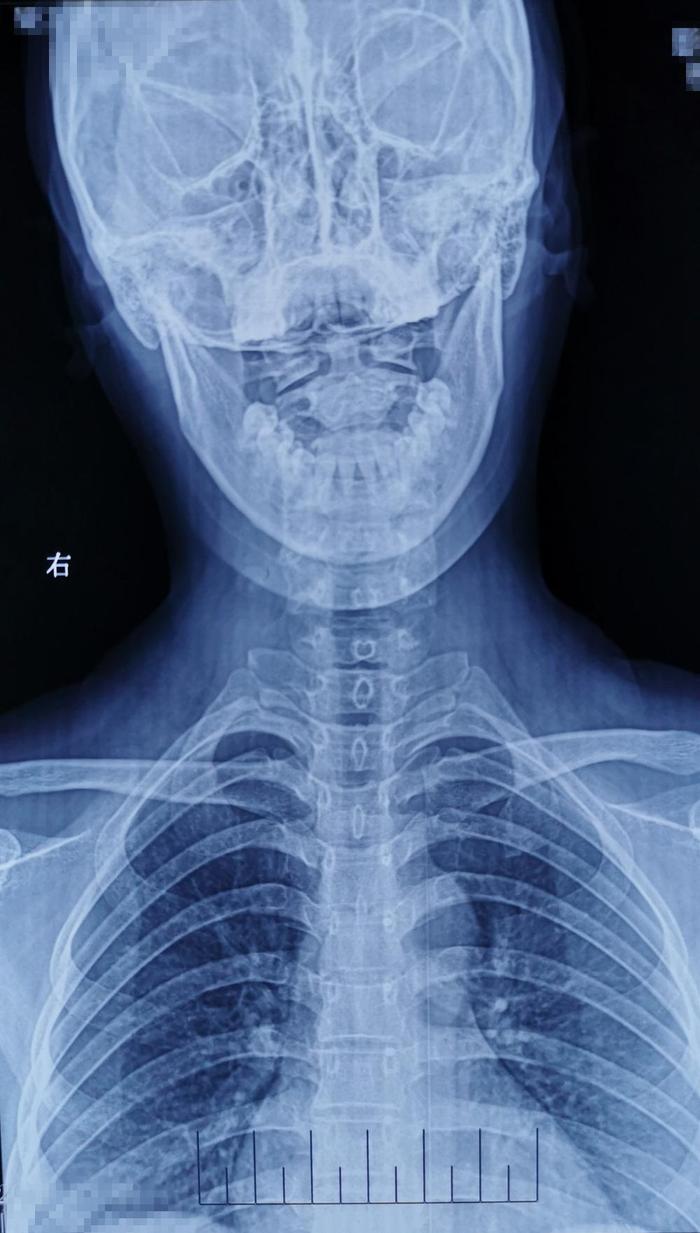

术后影像学资料: